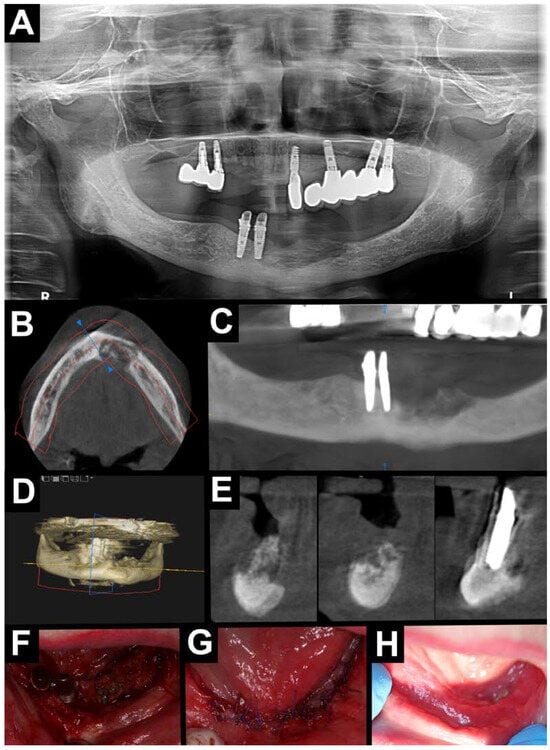

2.3. Surgical Procedure